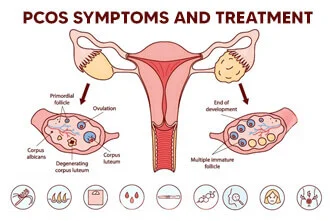

PCOS

Polycystic Ovary Syndrome (PCOS) is a hormonal disorder that affects 1 in 5 women in

India, often beginning in the reproductive years. Common signs include irregular periods,

acne, excessive facial hair, weight gain, and difficulty conceiving. While the exact cause

remains unclear, insulin resistance and hormonal imbalance are key contributors. In Jaipur,

lifestyle changes and increasing stress have led to a rising number of PCOS cases,

especially among young women.